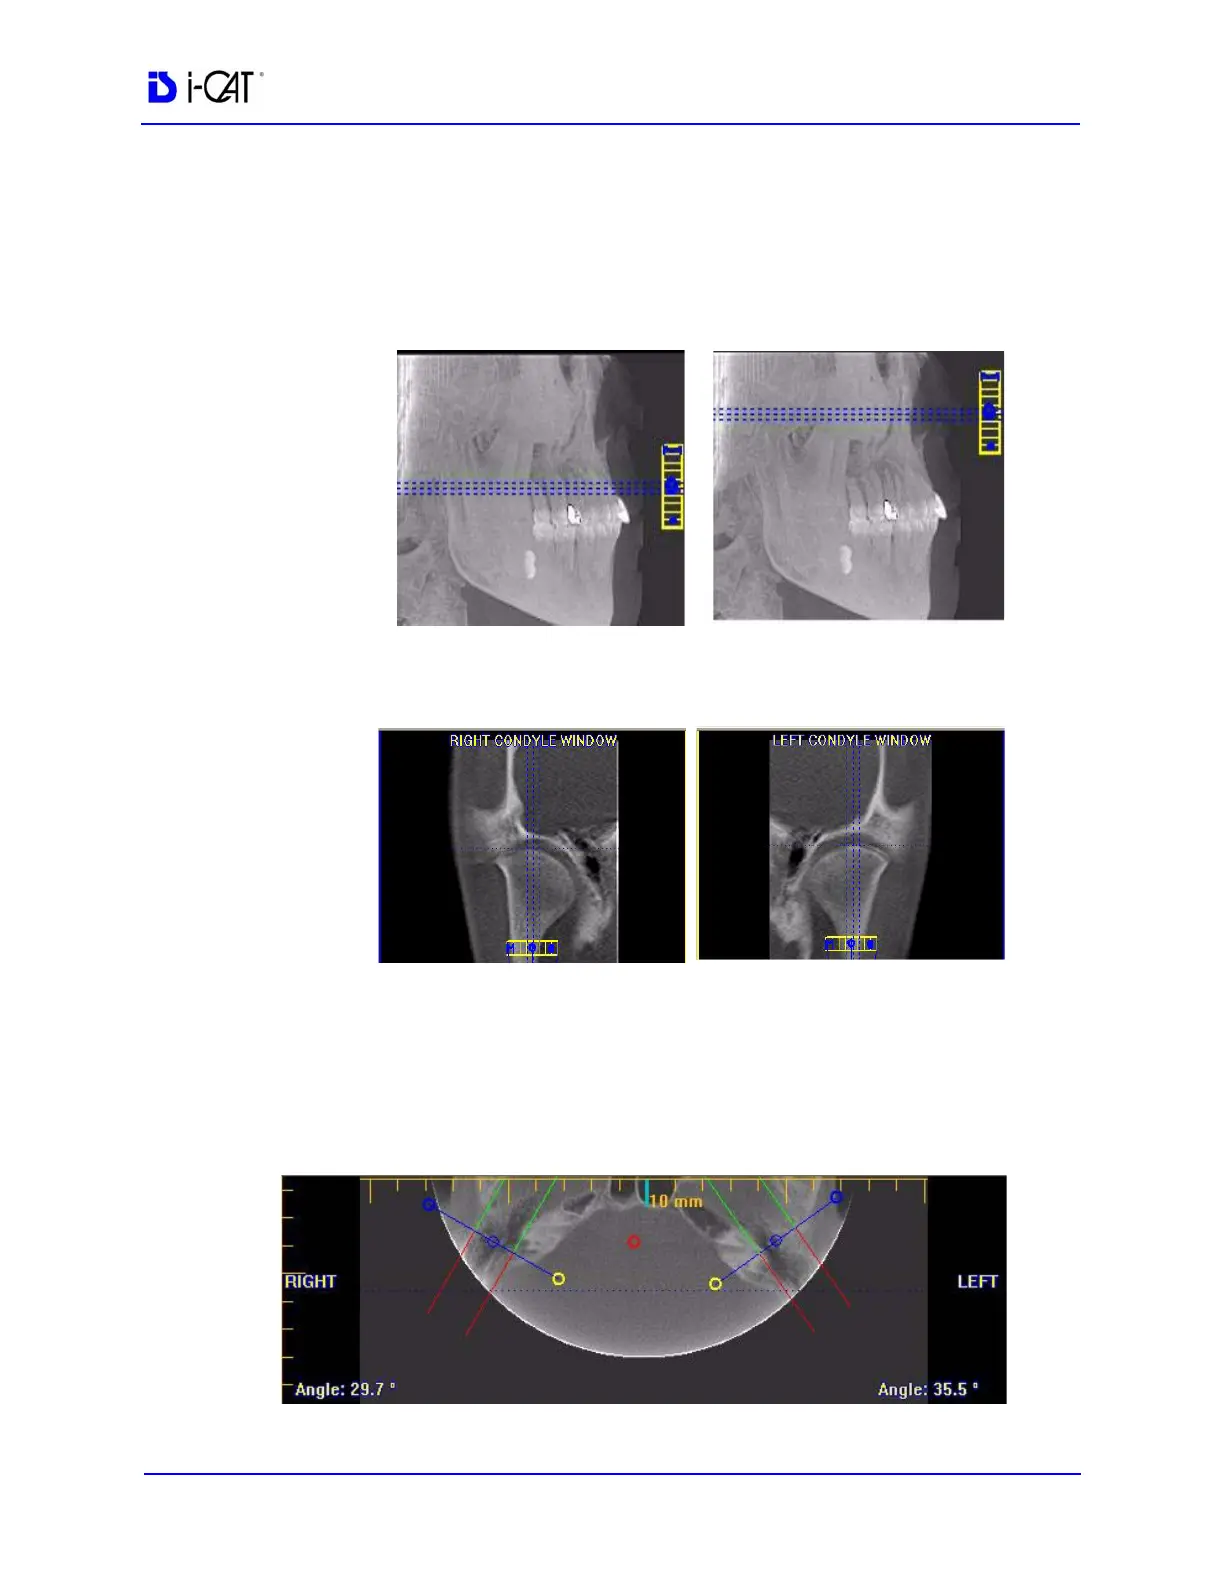

To use the TMJ Screen:

1. If necessary, pan the Axial (SMV) View (upper left) down in the

window to see the condyles. (See Pan Feature.)

2. Use the scroll bar center (O) tool to locate the condyles for

proper mapping.

3. Drag center (O) tools from the RIGHT and/or LEFT CONDYLE

WINDOWS to move the slice locations of the cross section

views.

4. Drag the solid circle tool (right edge of slice control) to adjust

the slice thickness of the cross section views.

To create lateral slices:

5. Drag the center blue circles on the Axial View to move the

corresponding Condyle Map.